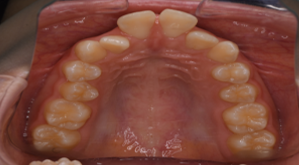

マウスピース型矯正装置(インビザライン)の症例

マウスピース型矯正装置(インビザライン)を使用した歯列矯正